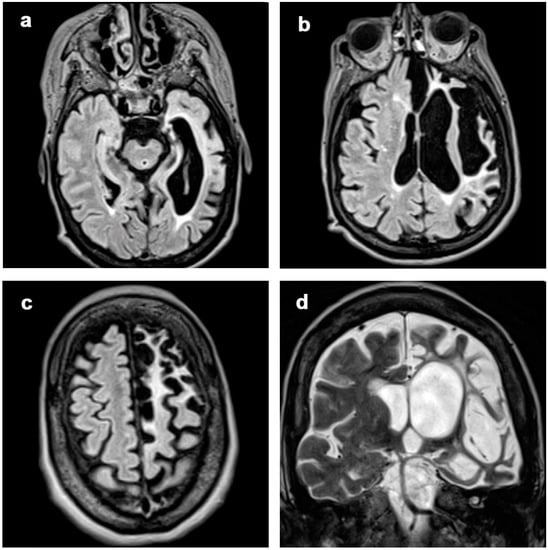

3.1. Atrophic Changes

3.2. Changes in Signal Intensity